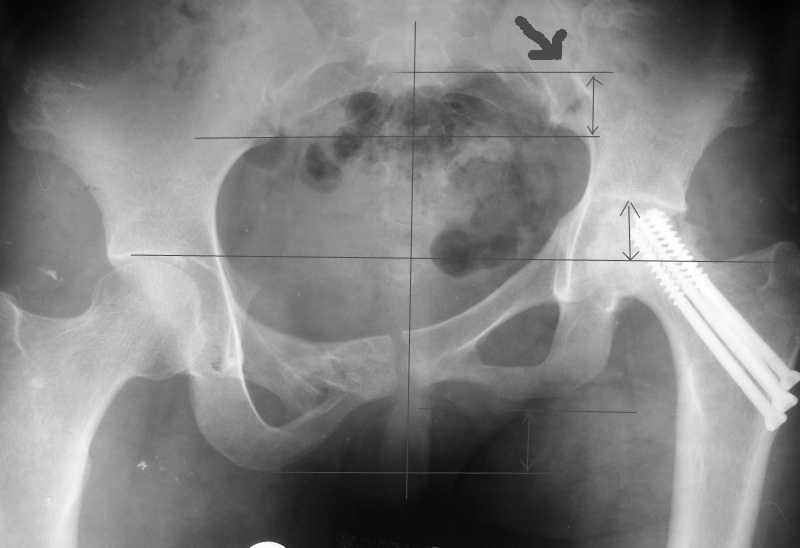

Привет, Макс. Не торопись, посмотри внимательно на истинную картину. Толстая стрелка указывает на нижний край смещенного кп сочленения.

Поэтому считаю, что Принять какое-либо решение без кт и дополнительных проекций неразумно.

разговоров нет, смещение значимое, какое оно было, такое и осталось. Будут проблемы и с сидением и с осанкой и т.д. Идеальным вариантом было бы, конечно, исправить деформацию, а потом запротезировать. Но... цена вопроса. сейчас деформация, судя по костной мозоли, стабильная, и таз несет основную свою функцию - опорную, явно КПС не болит. Превратить стабильную деформацию в нестабильную и потом ее исправить - задача непростая, но выполнимая. Оперативное лечение будет сложное, скорее всего многоэтапное и длительное. С определенными рисками, общехирургическими и специфическими, например несращение зоны остеотомий - нестабильный таз, ризидуальное смещение (в пределах 1 см вполне вероятно). Если считать, что на тазе укорочение см 3, остальные 5. все-таки сгибательно-приводящая контрактура. На протезе от контрактуры можно избавиться, да и см 2 удлинить за счет опила, головки. В такой ситуации решение должна принять пациентка и оно должно быть действительно информированным.